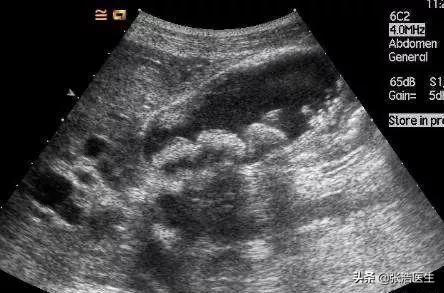

上の写真は、胆嚢内に大小複数の結石を認める超音波所見である。